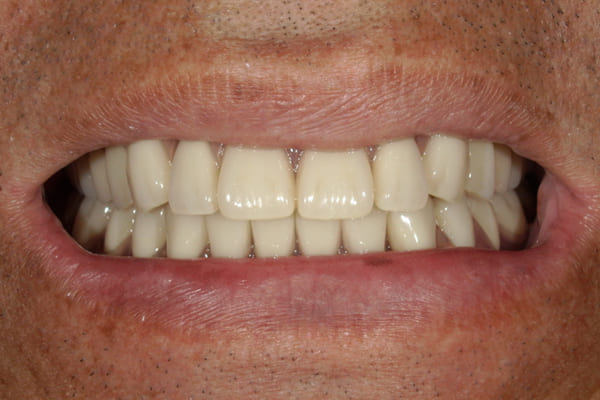

治療前は上下奥歯の入れ歯が削れていることで、かみ合わせが低くなり唇もつむった状態でした。

かみ合わせを適切な高さに戻したことで、本来の自然な口元へ。